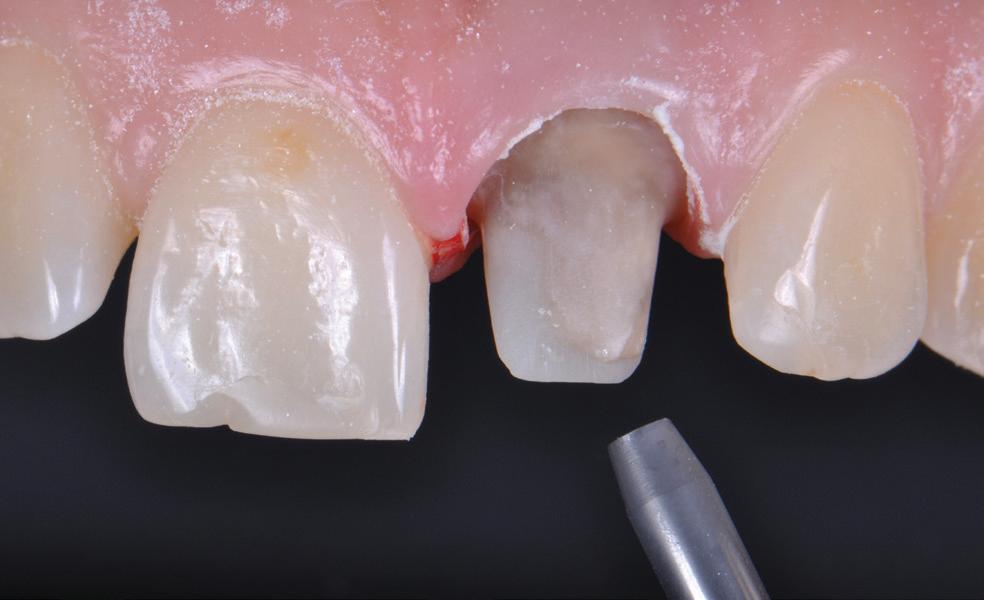

Adopting sharp safe methods is essential in all dental practices. The Ultra Safety Plus and Ultra Safety Plus Twist provides the dental team with the necessary tool to provide safe practice. If sharp safe habits are not expected of each team member, the risk of a sharp injury increases.